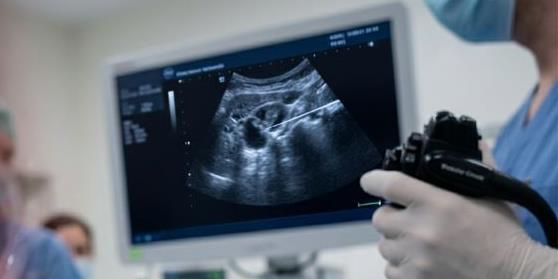

Investiciju od 971.000 KM podržao ZZO Zapadnohercegovačkog kantona.